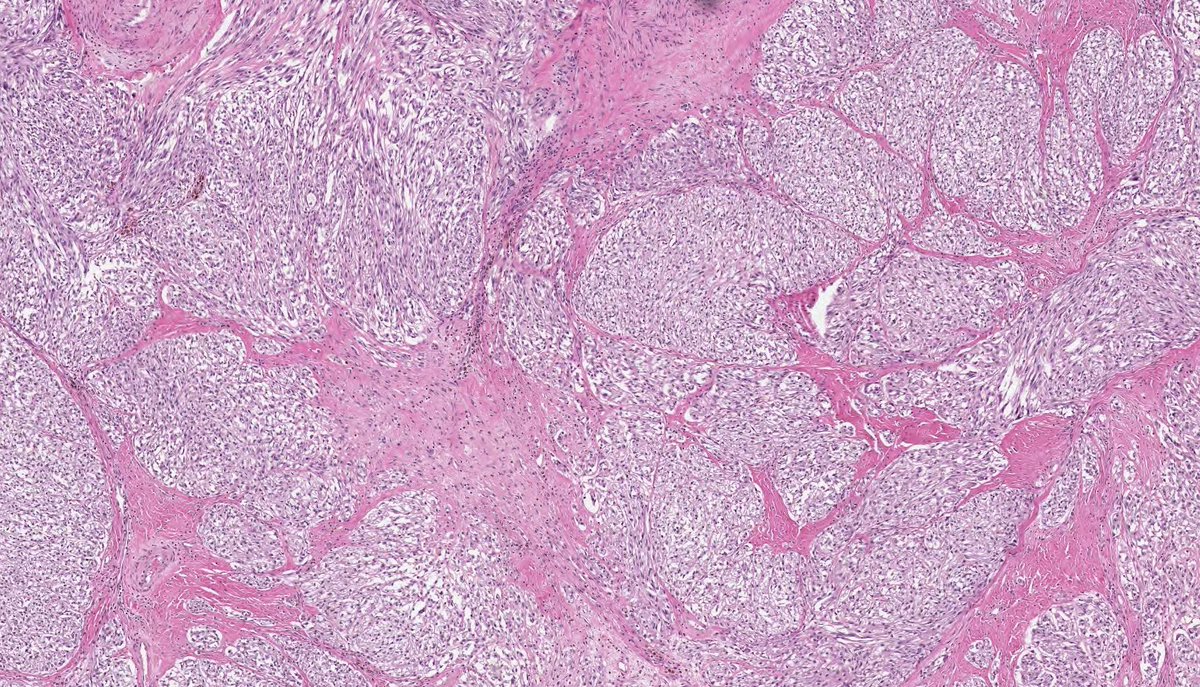

DEDIFFERENTIATED LIPOSARCOMA (myxofibrosarcoma-like variant). (FISH: + MDM2 amplification.) PMID: 10584701, 15832195, 23020289.